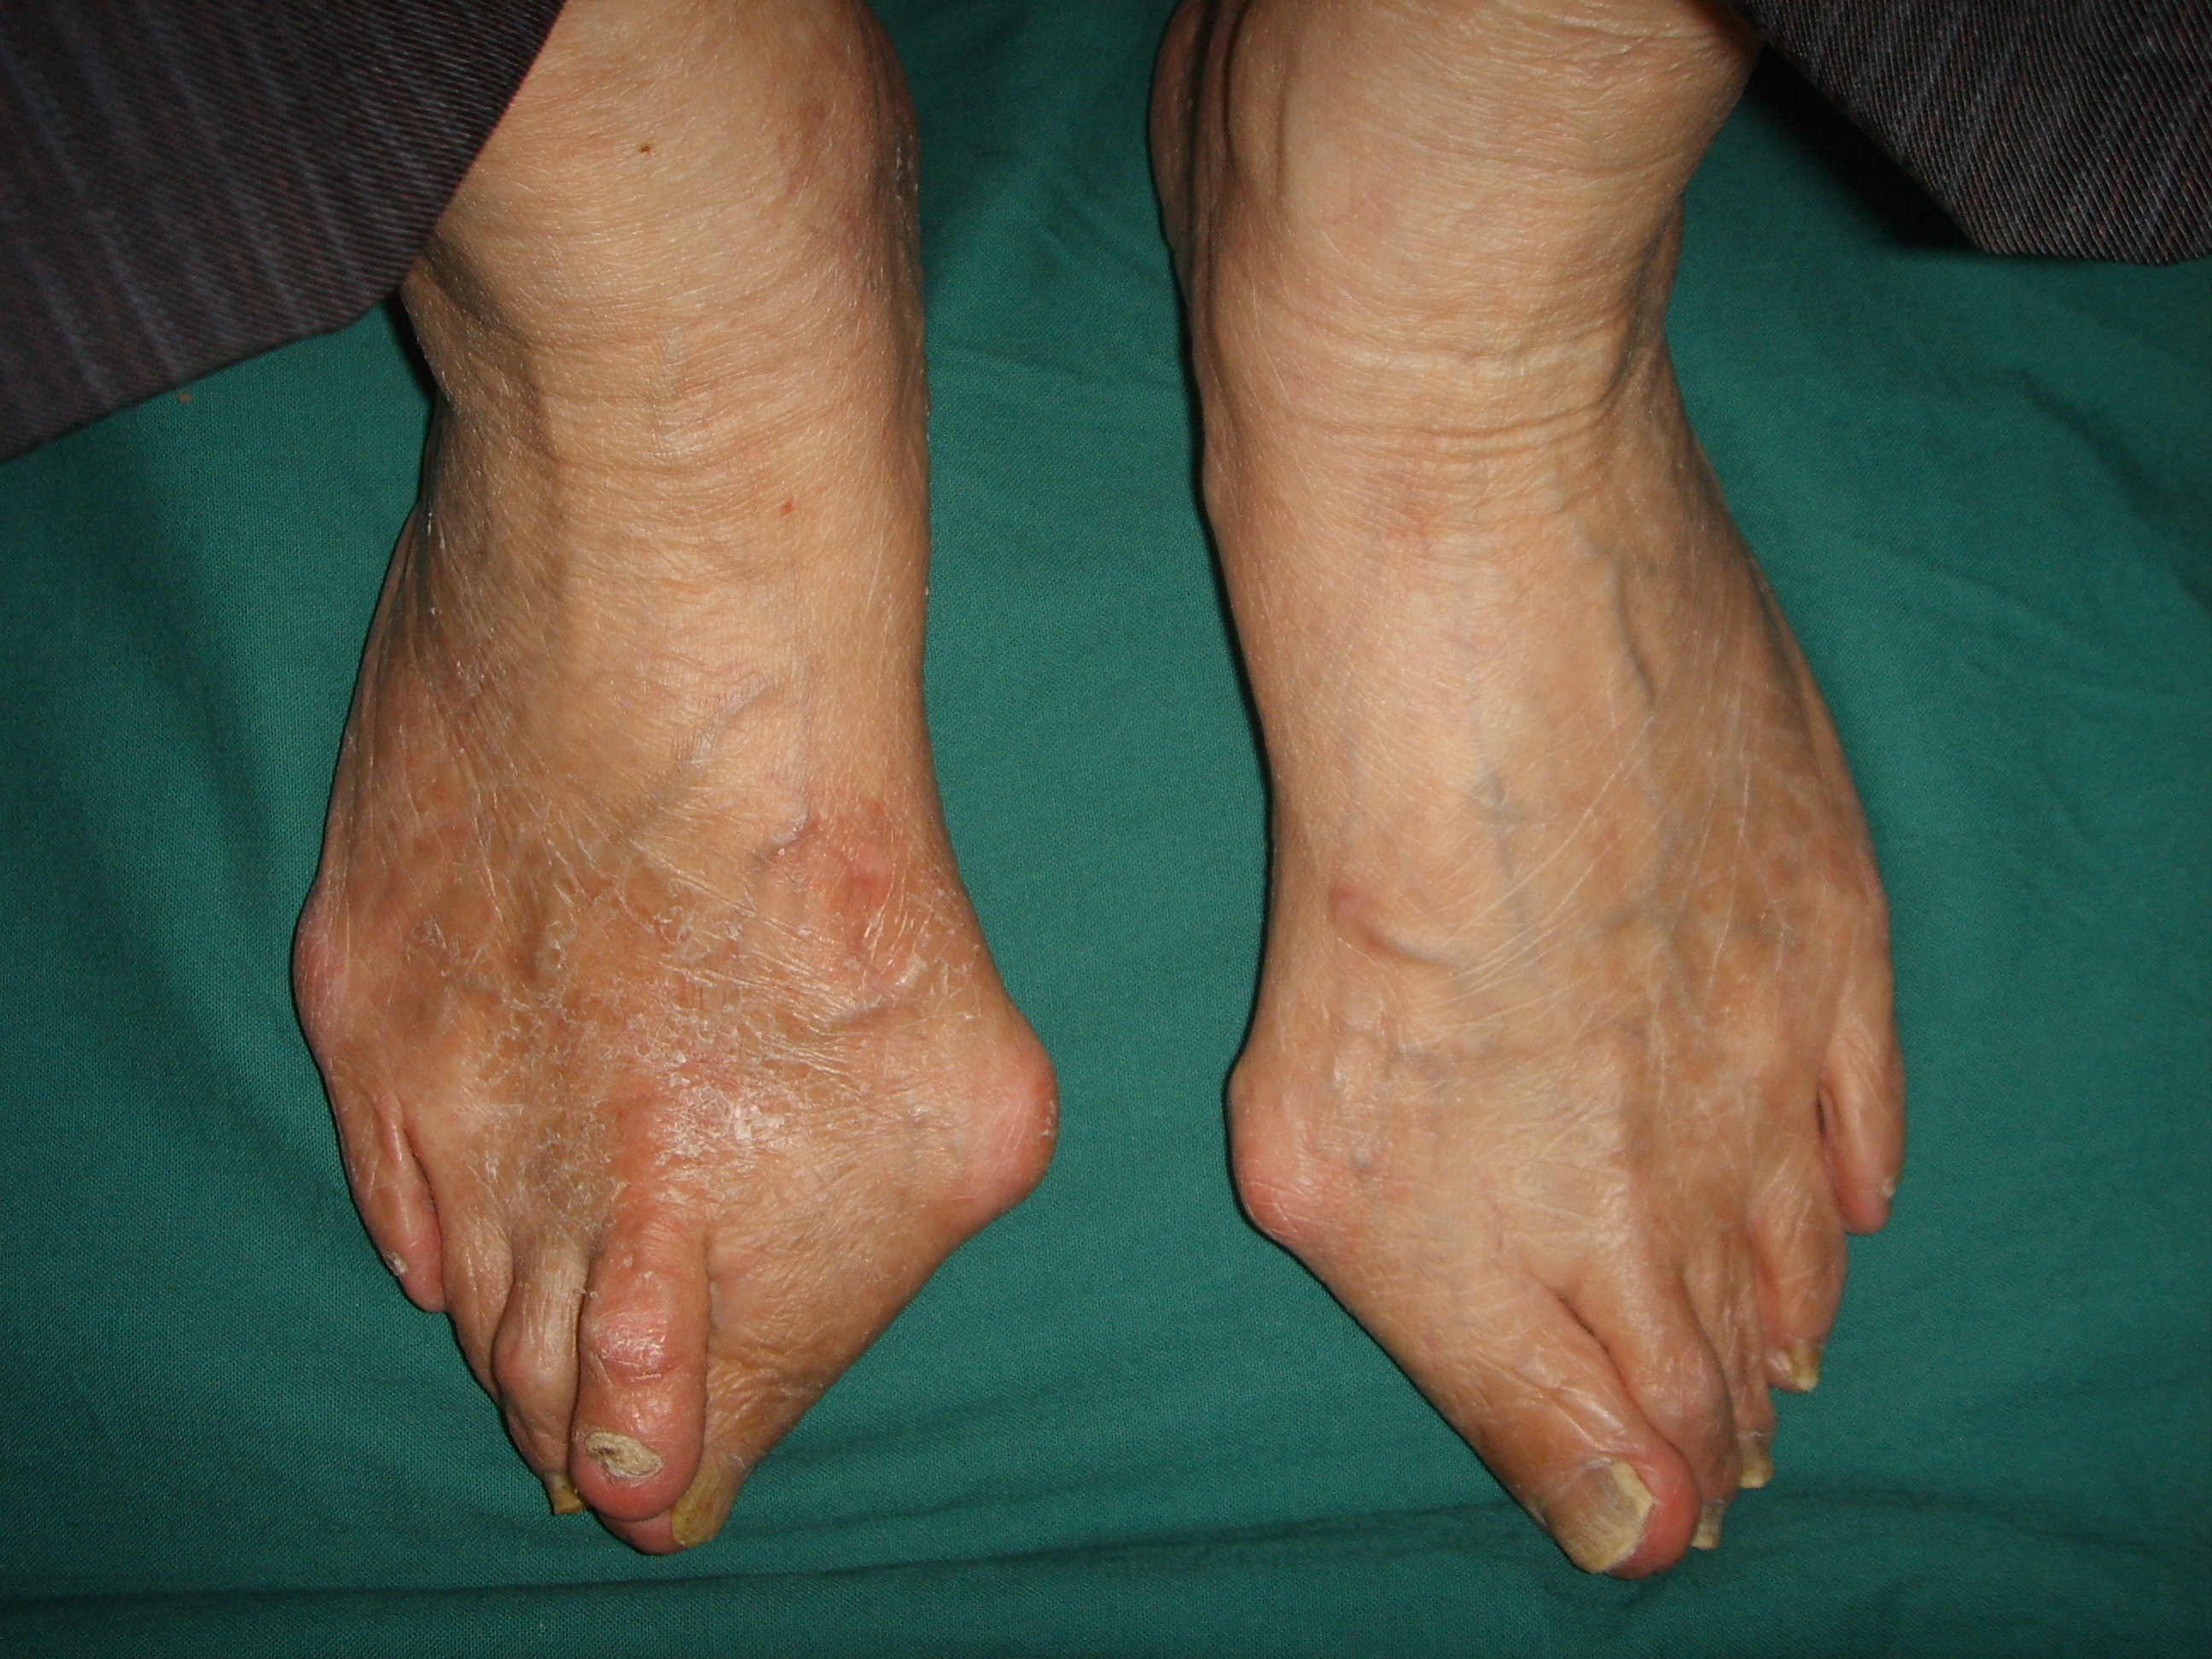

严重拇外翻

备注:上图的图一并非图三的术前,图一这样严重的拇外翻并不适合再做微创了。另外图三中大拇趾和第二趾之间的分叉,后续逐渐会合拢。